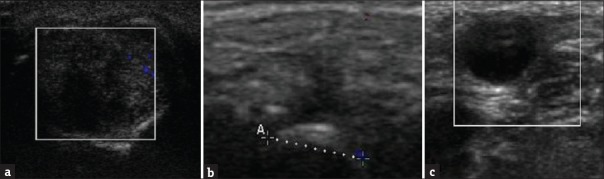

Introduction: Ultrasonography (USG) is found to be important in identifying various soft-tissue pathologies in the orofacial region. Therefore, its features should be studied and documented in these lesions so that a more appropriate provisional diagnosis can be made.

Aim: This study aims to study ultrasonographic features in various kinds of swellings in the orofacial region.

Materials and methods: The study grouped consists of 30 patients of both sexes (20 males and 10 females) with an age range of 15-70 years complaining of swellings in the orofacial region. All the patients in the study were explained the need of tests and subjected to clinical, ultrasonographic, and histopathologic examination. Sonosite Micromaxx sonography machine was used with a linear array transducer of 13-6 MHz frequencies. Ultrasonographic diagnosis is then correlated with clinical and histopathologic diagnosis. Chi-square test and contingency coefficient tests were used.

Results: A significant association was observed between clinical and ultrasonographic diagnoses (contingency = 0.872, P < 0.05) and between ultrasonographic and histopathologic diagnoses (contingency = 0.904, P < 0.05). There was 100% congruency between clinical diagnosis and ultrasonographic diagnosis in all the cases except in cases of cysts, abscess, and sialadenitis. Reliability of USG was found to be 97% in diagnosing all the cases with respect to histopathological diagnosis, while it was 90% with respect to clinical diagnosis.

Conclusion: USG was found to be a reliable diagnostic modality in the diagnosis of orofacial swellings.